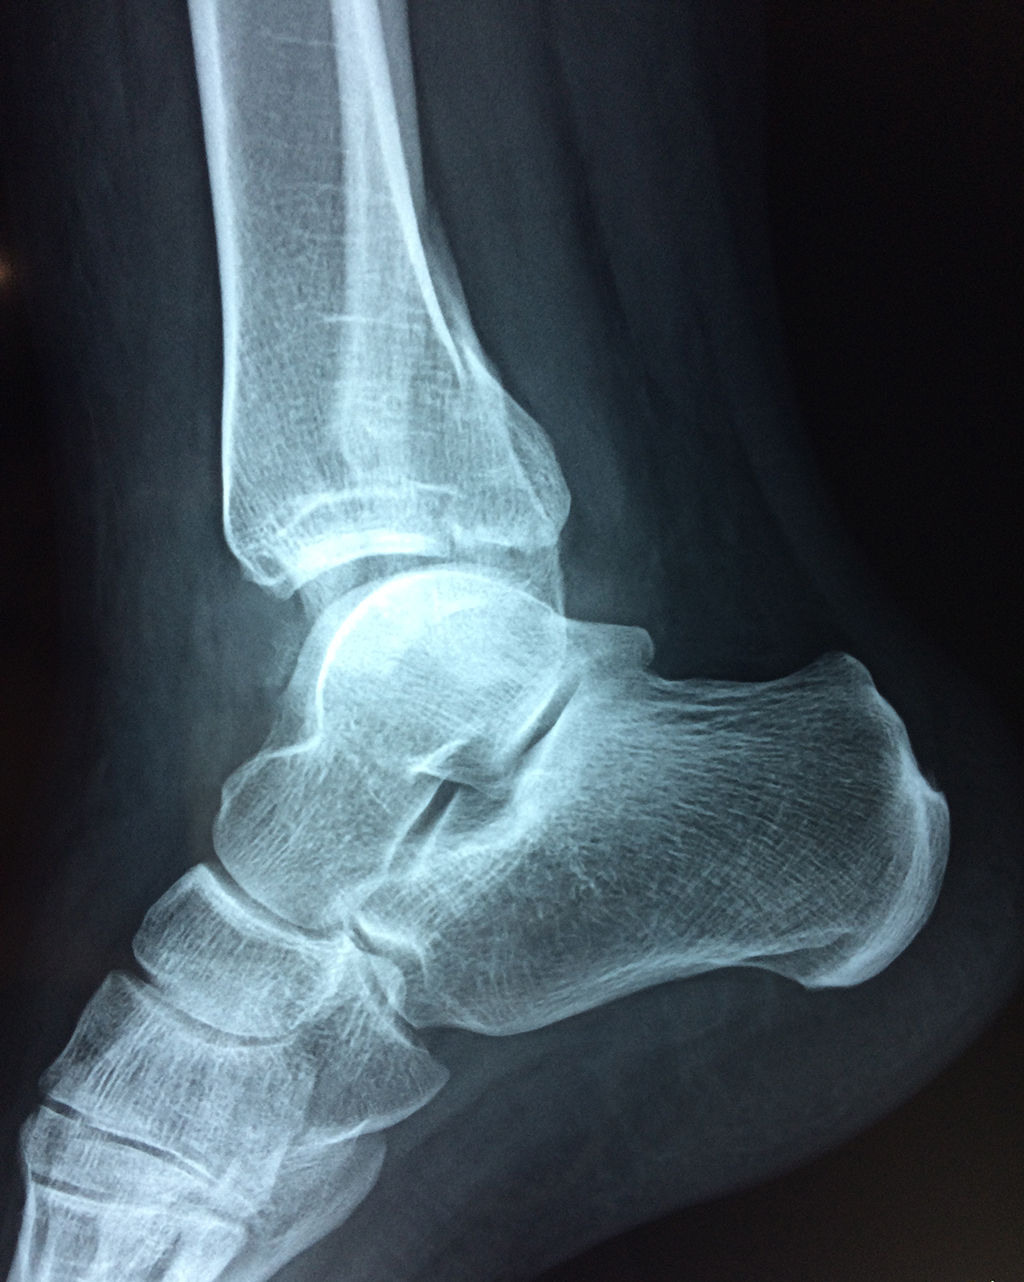

Una fractura de tobillo es la rotura de uno o más de los huesos del tobillo. Estas fracturas pueden ser:

- Parciales (el hueso está sólo parcialmente fisurado, no del todo).

- Completas (el hueso está perforado y está en 2 partes).

- Producirse en uno o ambos lados del tobillo.